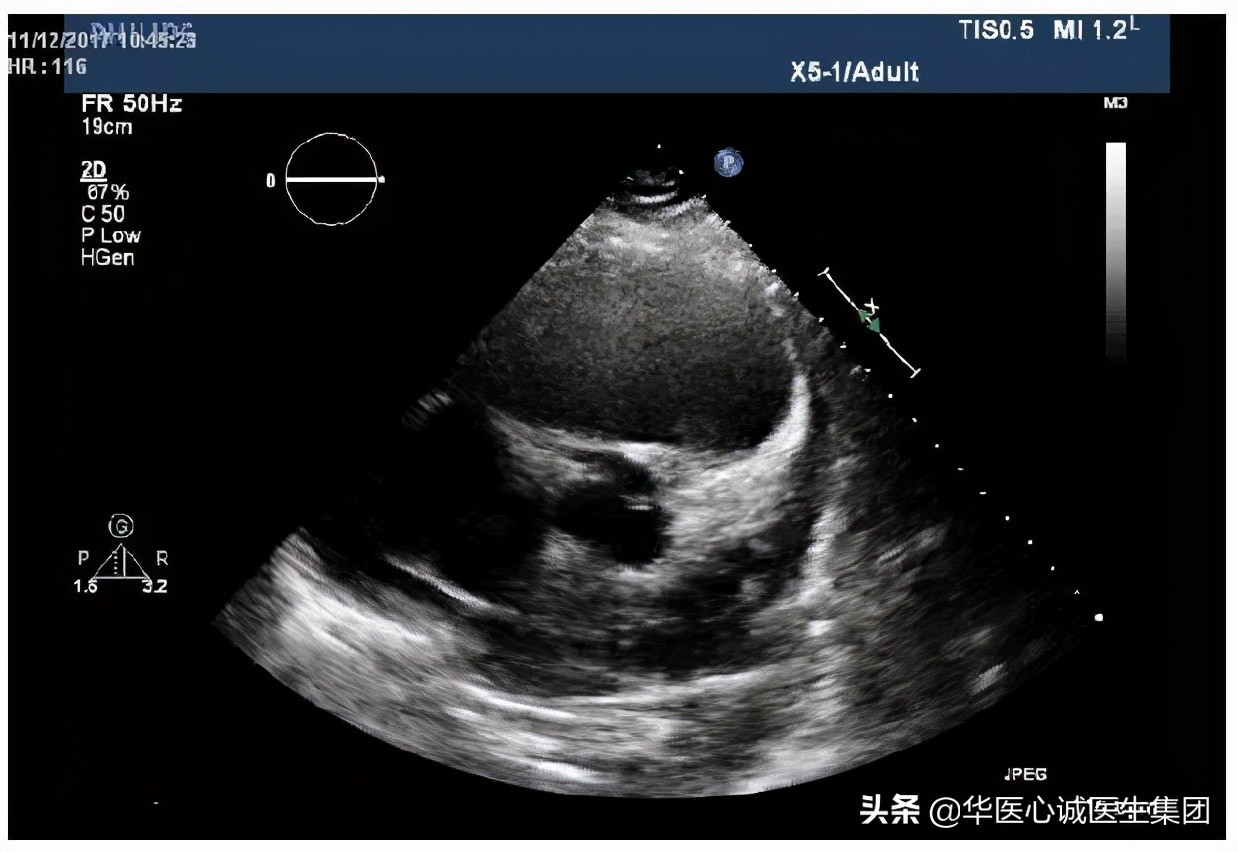

超声结果提示有心包积液,室壁增厚,约1.5cm。心腔扩大,左房、左室、右房均扩大,且收缩幅度下降。

- 大动脉短轴切面:右室明显增大,右室流出道和肺动脉均增宽。

- 左室短轴切面:可见心包积液,左室壁对称性增厚,室壁弥漫性运动减弱。上述问题可能是由慢性高血压引起的。